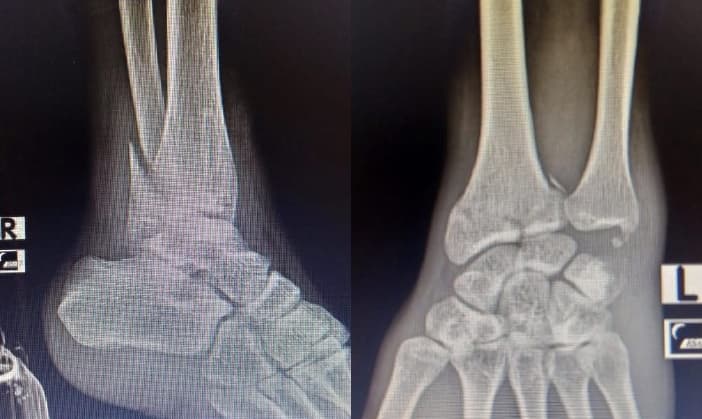

Long story short, saya mengalami kecelakaan motor yang terjadi pada pertengahan 2021 dan mengakibatkan tulang retak di pergelangan kaki kanan dan pergelangan tangan kiri.

Recovery selama 9 bulan lamanya, dimana saat itu saya sulit untuk berjalan dan juga sulit untuk mengetik.

Benar-benar istirahat di rumah, nyalain komputer pun jarang, ngetik pun cuma bisa pake tangan kanan :(

Akhir 2021, kaki dan tangan saya berangsur pulih. Awal 2022 merasa kaki dan tangan saya sudah benar-benar pulih total dan bisa beraktivitas seperti biasanya. Alhamdulillah :)